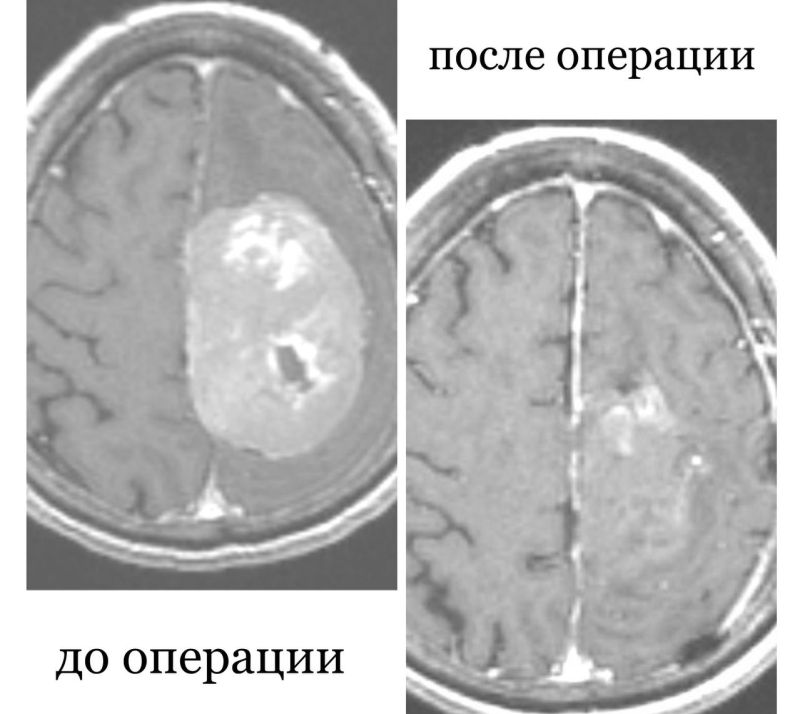

Жительница Бурятии с опухолью в мозге шесть лет отказывалась от операции

Опухоли головного мозга

Чем Отличается Киста От Опухоли В Головном Мозге